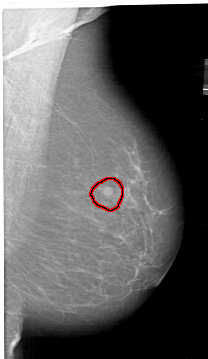

A_1409_1.RIGHT_MLO

RIGHT_MLO LINES 6451 PIXELS_PER_LINE 3736 BITS_PER_PIXEL 12 RESOLUTION 43.5 OVERLAY

FILE: A_1409_1.RIGHT_MLO.OVERLAY

TOTAL_ABNORMALITIES 1

ABNORMALITY 1

LESION_TYPE MASS SHAPE ROUND MARGINS ILL_DEFINED

ASSESSMENT 4

SUBTLETY 4

PATHOLOGY BENIGN

TOTAL_OUTLINES 1

BOUNDARY